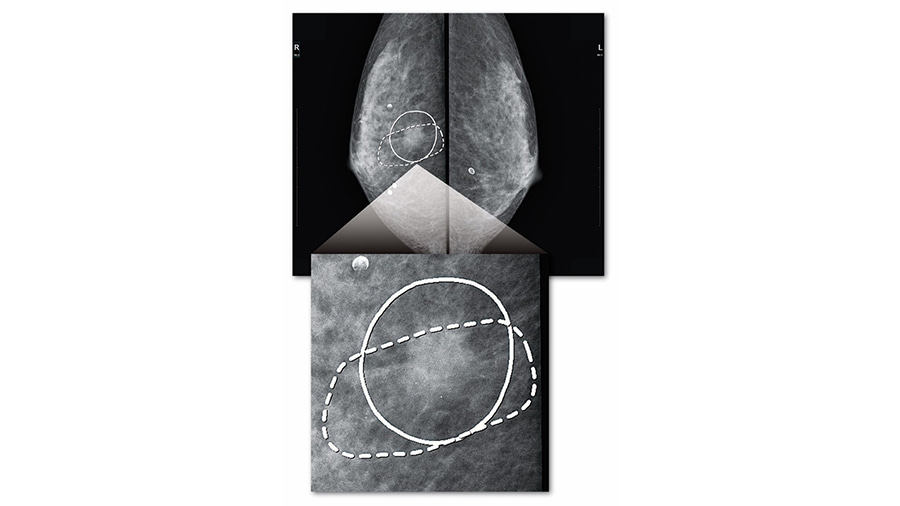

読影に優しいマーキング表示

簡単なボタン操作で、CADが検出したエリアを見やすい線で囲み表示し、画像の観察にともなうストレスの大幅な軽減に貢献します。